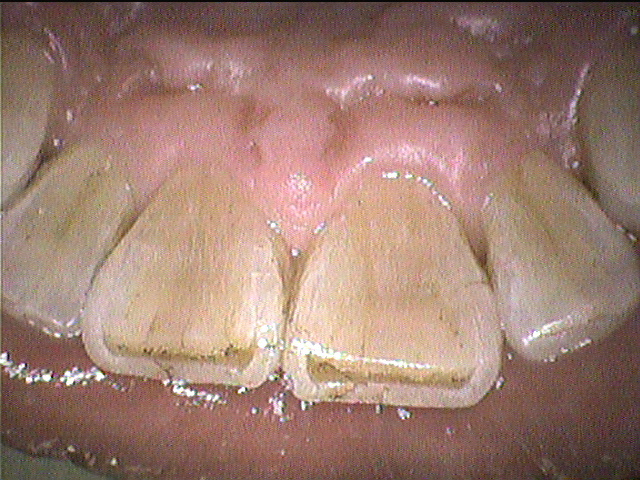

クリーニング後

下の前歯と上の前歯の裏側の写真です。

ステインに加えて歯石もついていましたが、しっかり除去し綺麗になりました。